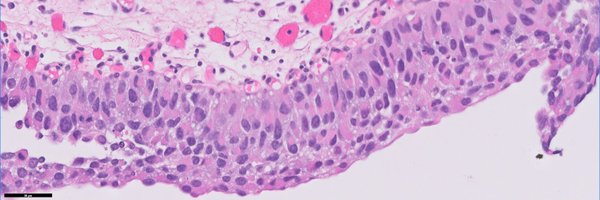

#GUpath #beautyinb9 mimic of prostate cancer on bx: 🔬basal cell hyperplasia